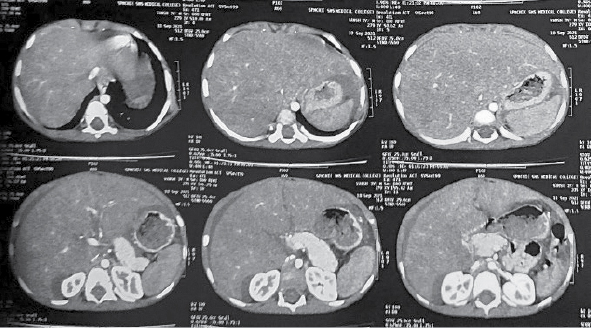

Contrast-enhanced computed tomography (CECT) scan of whole abdomen showed gross amount of free fluid in the peritoneal cavity, perihepatic and perisplenic region. Liver was enlarged with size approximately 126 mm. Portal vein appeared normal. Triple phase CECT abdomen done on Day 9 of admission showed mild hepatomegaly (128 mm) with heterogeneous contrast enhancement. Nonopacification of proximal portion of left and middle hepatic veins was seen. Moderate narrowing was seen at the origin of right hepatic vein and there was delayed faint opacification. Intrahepatic IVC appeared small in caliber. Moderate free fluid was seen in abdomen and pelvis (Fig. 2).

Figure 2. Triple phase CECT abdomen showing BCS.